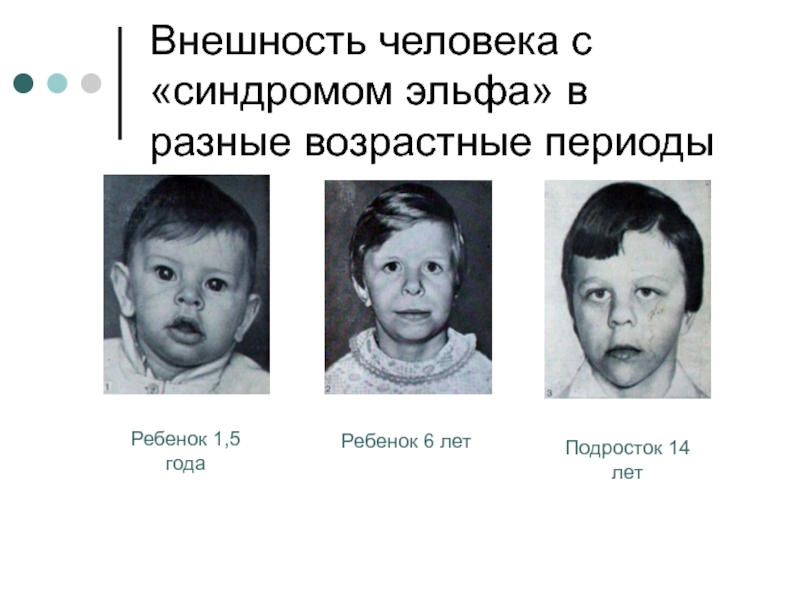

Визуальные материалы, связанные с болезнью Горхема-Стаута